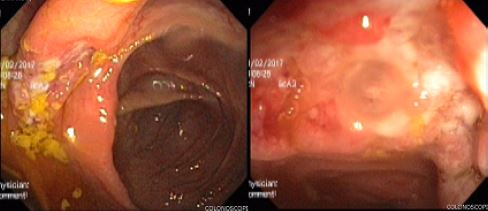

Cinco años más tarde del diagnóstico de TB latente, el paciente presentó episodios de dolor abdominal en el mesogastrio, asociado con rectorragia, hematoquecia, sin diarrea, de casi 3 semanas de evolución, por lo cual consultó a urgencias. El hombre fue hospitalizado y le realizaron una colonoscopia total, donde se identificaron proctitis y úlceras profundas transversales que afectaban el colon derecho; además de severos cambios inflamatorios con aspecto nodular en la válvula ileocecal e ileon distal ( figura 1).

El reporte de las biopsias mostró inflamación crónica activa severa, ulcerada, con granulomas sin necrosis caseosa, por lo cual se le indicaron coloraciones especiales Ziehl-Neelsen, Ziehl-Neelsen modificado (estas para descartar presencia de bacilos ácido alcohol resistentes y coccidias), tinción de PAS, tinción de plata metenamina de Grocott (estas para descartar presencia de hongos patógenos); además, inmunohistoquímica de citomegalovirus. Todas estas pruebas resultaron negativas. Se le dio el alta hospitalaria con sospecha de EC. Se dejó tratamiento con prednisolona a 40 mg por día durante 2 semanas, luego una reducción gradual de 5 mg cada semana hasta suspender. En estudios adicionales, se le realizó una cápsula endoscópica, que indicó una ulceración estenosante en yeyuno. Los reactantes de fase aguda como la velocidad de sedimentación globular, 41; reacción en cadena de la polimerasa, 2,5 (VR hasta 0,8), y calprotectina fecal, 1100 µg/kg/heces (VR 50 µg/kg/heces), se encontraban elevados. Con estos hallazgos se decidió reducir el intervalo de aplicación del adalimumab a 40 mg cada semana, y se le añadió azatioprina a dosis de 2 mg/kg/día (150 mg/día). Un mes después del inicio de este tratamiento, presentó un cuadro de fiebre, diaforesis nocturna, tos seca, por lo cual se hospitalizó y se diagnosticó con tuberculosis miliar ( figura 2). Múltiples adenopatías mesentéricas (con evidencia de granulomas caseificantes), y con evidencia de actividad endoscópica. El diagnóstico microbiológico fue mediante fibrobroncoscopia y lavado bronquioalveolar (secreciones pulmonares).